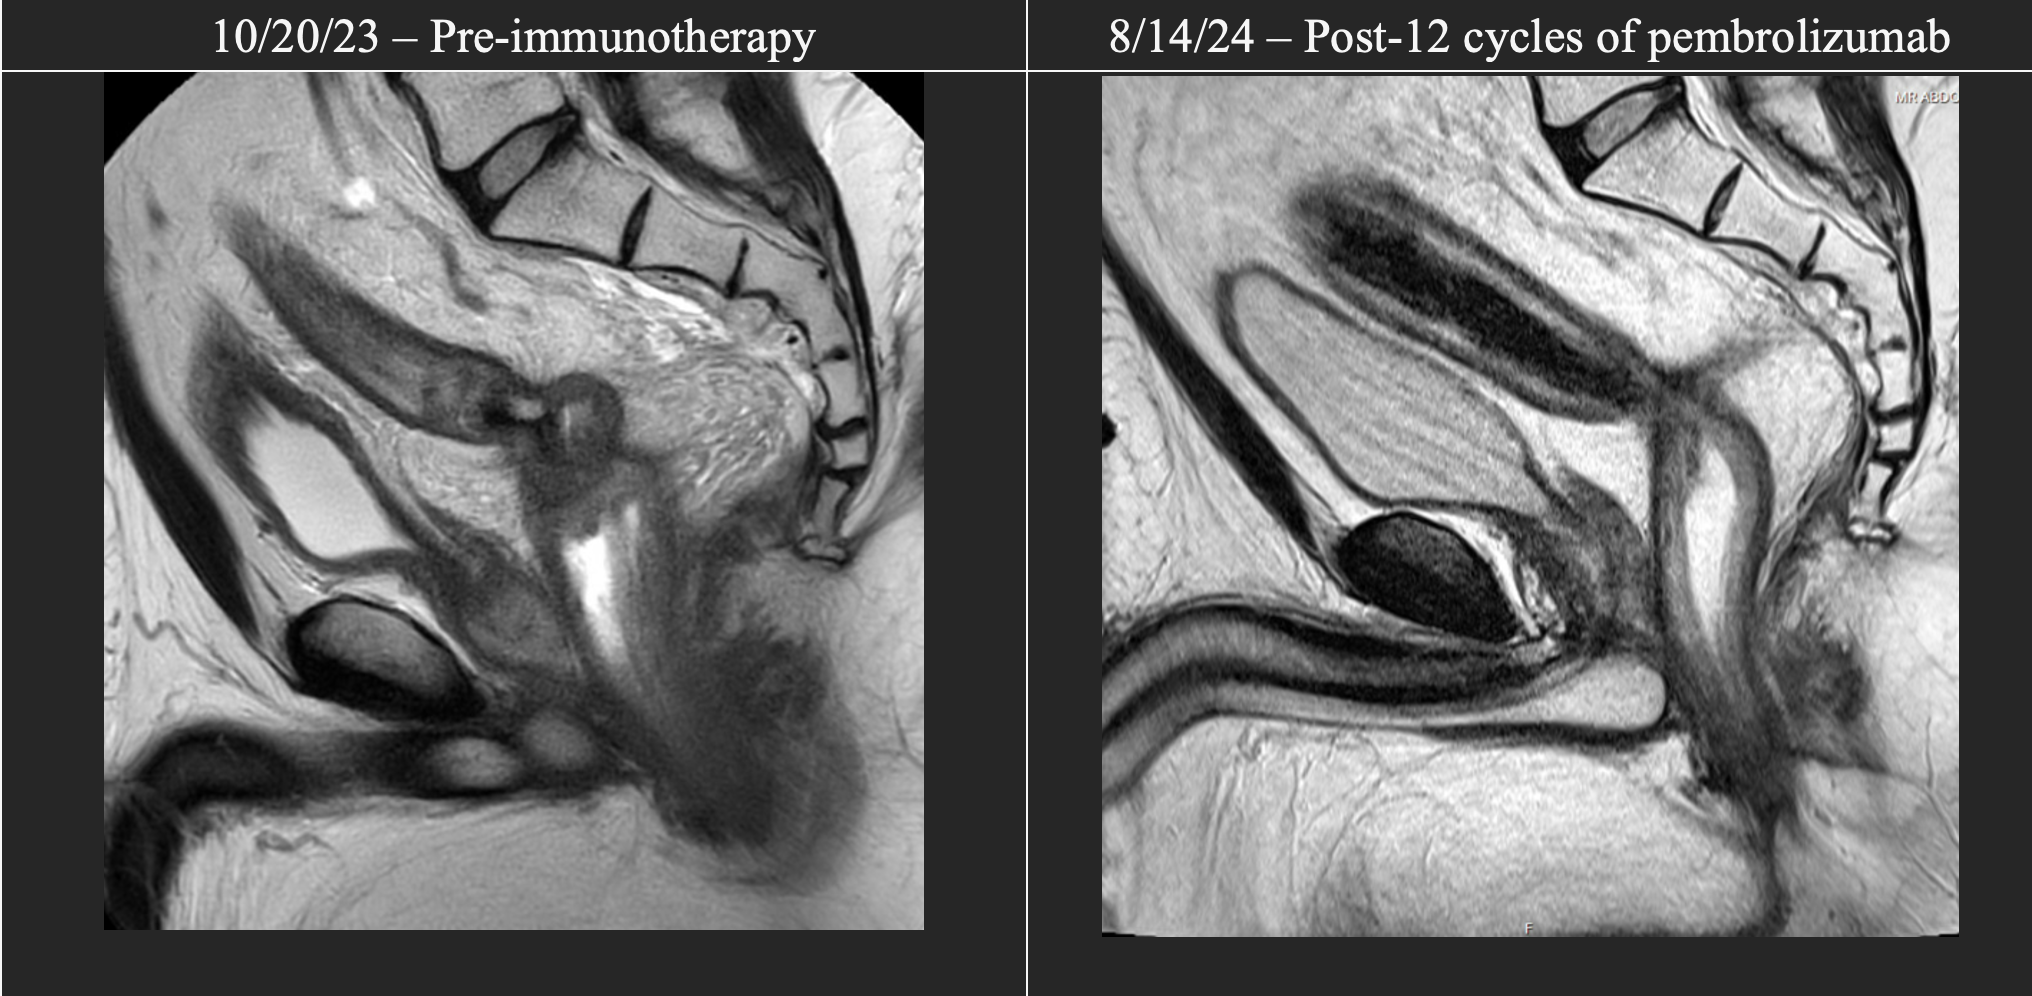

Magnetic resonance imaging-T2 scans of patient in case #1 before immunotherapy initiation and after 12 cycles of pembrolizumab. Interval imaging demonstrated partial but incomplete response of the tumor.